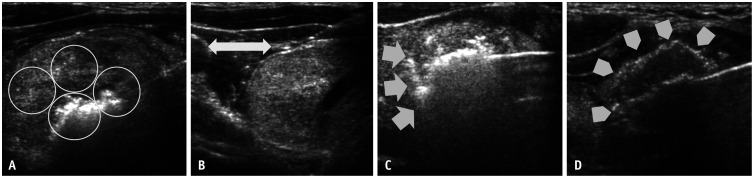

Abstract Image